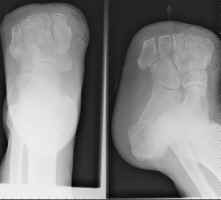

Amputations proximal to the transmetatarsal level often result in considerable gait

problems during walking. This is secondary to the loss of support and push-off.

When performed (often for the diabetic patient and in certain traumas), recent

improvements in preoperative testing (e.g. ultrasound) allow for a relative high accuracy

in predicting which patients will heal. The principle complication of the Lisfranc

amputation is a tendency towards an equinus deformity from the loss of dorsiflexor

attachments. If severe, such a deformity may require repeat amputation at a higher

level.